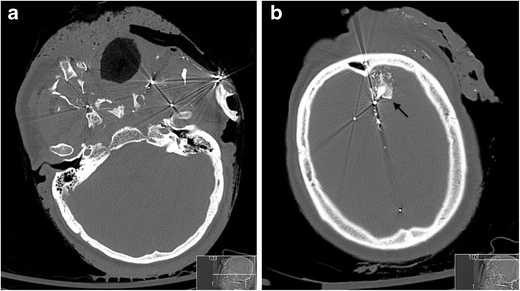

a Axial non-contrast CT face image on bone-window setting of a 51-year-old man with self-inflicted shotgun injury to the face. The high mortality of self-inflicted shotgun injuries to the face relates to the high tissue-destructive energy of a shotgun fired at close range to the target (compared with long range) as well as the “billiard-effect” created by the shotgun pellets. In this case, the marked avulsion of the facial soft tissues is evident as well as the marked bone disruption and fragmentation of the facial and mandibular skeleton. b Axial non-contrast CT image through the brain on bone-window settings of the same patient as in a. An in-driven canine tooth and attached alveolar bone fragment (black arrow) has penetrated the left frontal lobe, in addition to some of the shotgun pellets. The in-driven fragments of facial skeleton in orbito-facial projectile penetrating injury may become significant secondary damaging projectiles, particularly to the brain